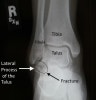

X-ray : 거골경 골절(Talus neck fracture)